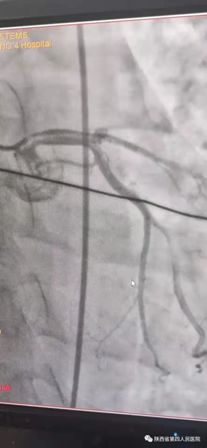

(术前造影) (术后)

11月10日15时58分左右,家住医院附近的中年男性辛先生在家人陪伴下来到我院急诊内科门诊诊室,满头大汗,捂着胸口说胸痛、胸闷、气短,急诊科主治医师钟高亮立即安排床位进行留观给予吸氧、心电监护、查体,心电图提示:1、窦性心律;2、室性早搏;3、急性下壁、前壁心肌梗死,诊断:急性冠脉综合征、心肌梗死。随后患者在急诊科留观室病情突然加重,意识丧失、四肢抽搐、面色苍白、全身大汗、呼吸急促,心电监护提示心室颤动,判断其可能为急性心肌梗死心源性休克,急诊科和心内科医生立即行胸外心脏按压,电除颤三次等对症治疗,立即启动胸痛患者抢救应急预案,开启绿色通道,和患者家属谈话,为其迅速办理入院手续,给予升压补液扩容等抢救治疗,积极完善术前准备,联系医务科和介入导管室,于16时22分将患者转运至导管室,心内科主任、主任医师王选琦带领团队副主任医师孙耀林、王崇振,主治医师马艳萍共同夺取患者最宝贵生命时间,为患者选择了从下肢股动脉穿刺造影,从穿刺到开通血管用仅仅只用了十一分钟。16时33分顺利完成PAG PCI支架植入术后成功再通,患者转危为安,随后入住心血管内科CCU病房继续治疗。